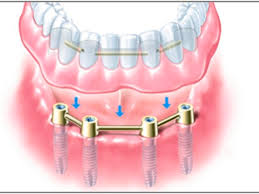

Https Www Drzieger De Friadent1 Pdf

Https Www Drzieger De Friadent1 Pdf from